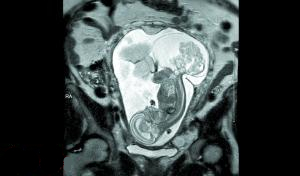

美國(guó)德克薩斯州的婦女瑪格麗特·伯默懷孕16周時(shí)去做常規(guī)產(chǎn)檢,發(fā)現(xiàn)胎兒患上了一種罕見(jiàn)的腫瘤,可能對(duì)胎兒構(gòu)成致命威脅?,敻覃愄仉S后在德州一家醫(yī)院接受手術(shù),醫(yī)生打開(kāi)子宮為胎兒摘除腫瘤,又迅速將胎兒送回子宮并縫合。12周后,寶寶“第二次”出生。

這是瑪格麗特的第三個(gè)女兒,她已經(jīng)給寶寶起好了名字,叫琳莉。骶尾部畸胎瘤是一種妊娠期腫瘤,通常長(zhǎng)在胎兒的尾骨部分?;疾『螅[瘤會(huì)和胎兒爭(zhēng)搶有限的供血,胎兒心臟跳動(dòng)就會(huì)受到影響,可能會(huì)致命。

琳莉23周零5天的時(shí)候,瑪格麗特在德克薩斯兒童醫(yī)院接受了手術(shù),這時(shí)的腫瘤都快比琳莉大了。手術(shù)共進(jìn)行了5個(gè)小時(shí),“摘除腫瘤時(shí)我們做得很快,只花了20分鐘。較花時(shí)間的是打開(kāi)子宮。我們不想讓媽媽的健康受影響,所以進(jìn)行得很仔細(xì)”。

由于腫瘤已經(jīng)很大,要取出來(lái)還是需要切口,摘除腫瘤時(shí)胎兒完全離開(kāi)了瑪格麗特的子宮。當(dāng)時(shí)琳莉才大約540克重,在空氣中暴露了約20分鐘?!八械难蛩渤鰜?lái)了,非常神奇?!笨ㄋ贯t(yī)生說(shuō)。